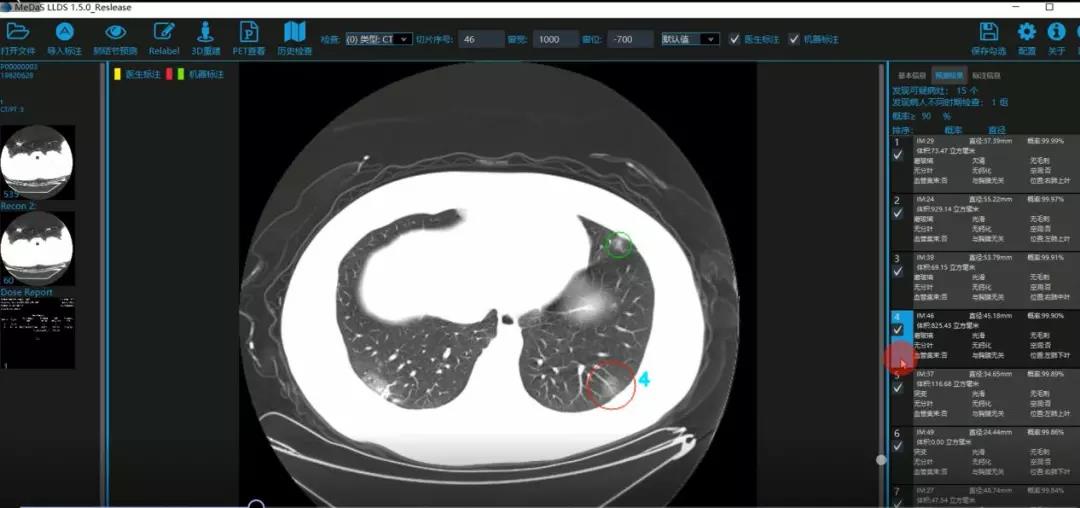

医护人员的好帮手:基于深度学习的新冠肺炎早期检测筛查系统

西电bat365在线中国登录入口智能软件与系统新技术研究所副教授张亮的爱人是西安交通大学第二附属医院抗疫一线的影像科医生,疫情发生以来,他们讨论最多的就是新型冠状病毒感染者的早期诊断问题。作为一名医护家属,身为高校科研工作者,张亮深知快速准确地诊断新冠肺炎早期患者对控制和防治疫情的重要性和挑战性。他与团队成员主动出击,通过远程网络会议,在前期医学影像处理的研究基础上加速科研攻关,反复讨论方案,屡次设计模型,与上海宽带技术及应用工程研究中心、上海交通大学医学院附属瑞金医院等合作单位的人员多次标注整理患者肺部CT影像数据到深夜。与此同时,他们依托上海瑞金医院、西安交通大学第二附属医院等的新冠肺炎疑似、确诊患者肺部CT影像,通过综合分析新冠肺炎患者的肺部CT影像特点(磨玻璃、体积大小、位置等特征),张亮团队加快技术攻关,设计开发了基于深度学习的新型冠状病毒的早期检测筛查模型系统。

对应新冠肺炎CT病灶检测效果

令人欣喜的是,通过对实际门诊数据排查测试,该模型可以减轻医护人员近80%的工作量,新冠肺炎患者的检测召回率超过95%。目前,模型系统正在进行最后的调试工作,很快投入到“战疫”一线,缓解医护人员紧缺、确诊检测工作耗时较长等问题,减少医护人员的工作时间和劳动强度,提高工作效率。